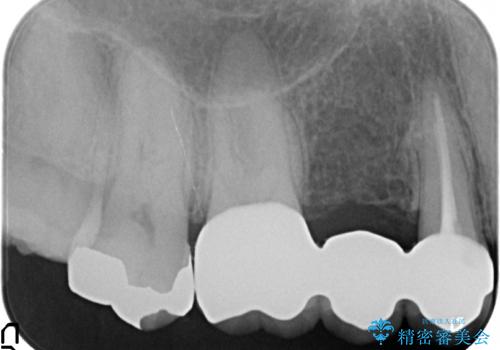

- 右上の奥歯でものを咬むと痛むので診て欲しいといらっしゃった方の症例です。

診査の結果、歯根が破折しており保存不可能だったため抜歯し、ブリッジによる補綴を行いました。